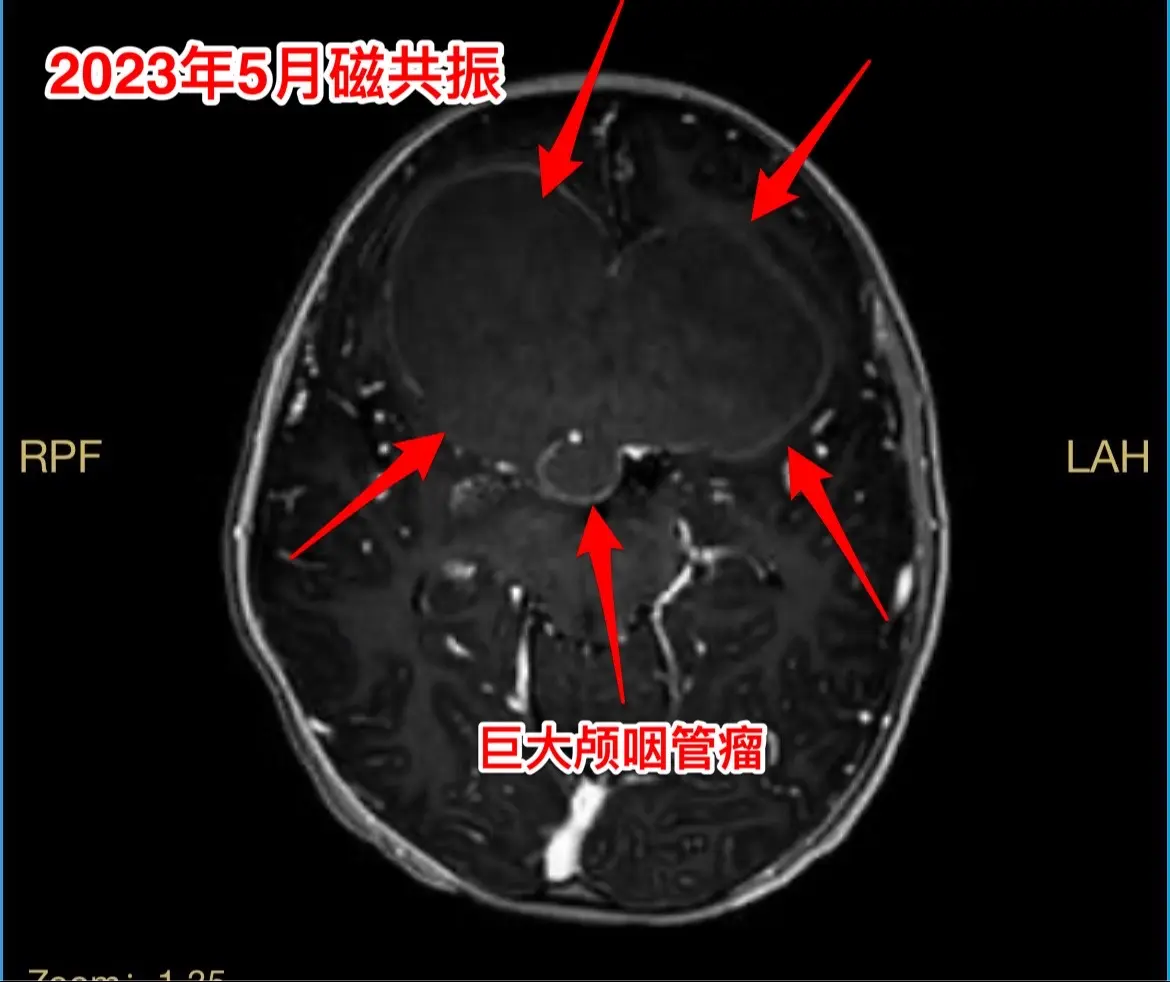

今日两个颅咽管瘤手术。1,6岁男孩子,安徽宿州人。2023年5月因视力下降发现了脑部长了巨大颅咽管瘤,见图1。家长曾经通过微信找我看过,最终选择在上海某医院行手术治疗,手术后出现右侧偏瘫,经过康复治疗后能勉强走路,但是右手还不能拿笔写字。2023.12磁共振就显示颅咽管瘤复发了(多块肿瘤复发)。2024.10又出现视力下降,故来找我作手术。今天手术中发现有四块较大的肿瘤,同时有很多个小钙化。所见肿瘤均顺利切除了。对比两次手术前的磁共振,可以说第一次手术更容易达到完全切除肿瘤,很遗憾,那一次机会错过了。 2,9岁男孩子,江苏盐城市的。因头痛、呕吐检查发现脑部有典型的颅咽管瘤,伴有脑积水。病人到我科住院后经用甘露醇和地塞米松后头痛、呕吐症状消失,能正常吃喝。今日作了开颅手术,顺利切除肿瘤。